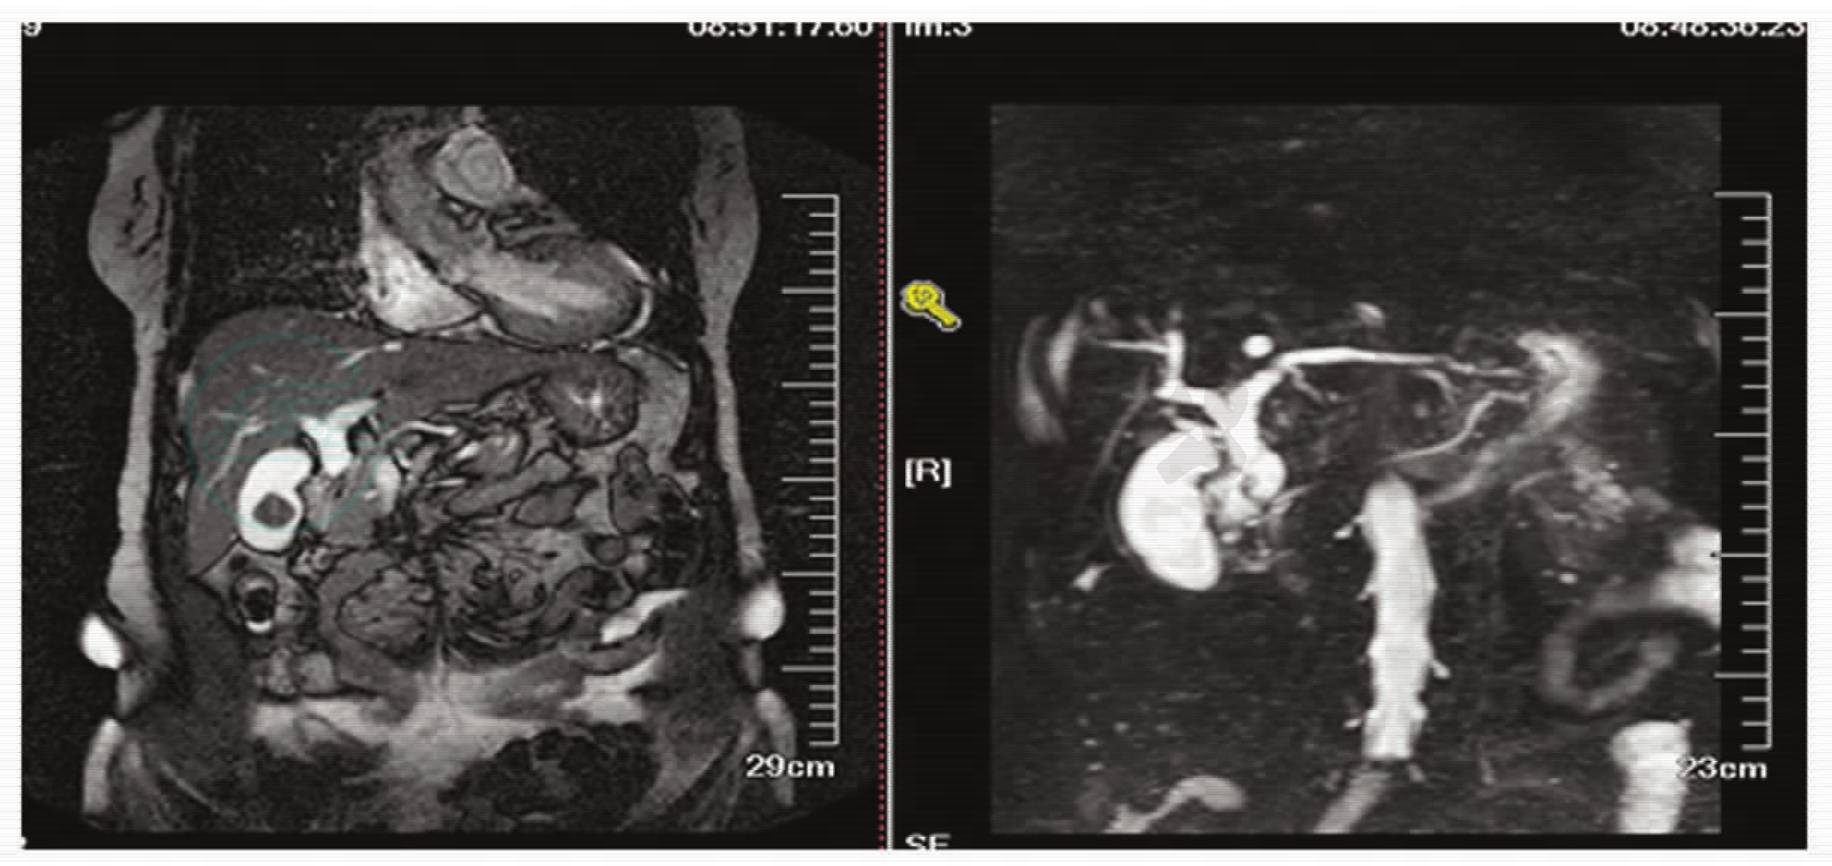

2.患者经上述治疗后,腹痛频率及程度逐渐减轻,体温波动在36.5~36.8℃之间,复查血常规正常,ALT及AST逐渐下降,胆红素正常,白蛋白28.8g/L,总蛋白58.2g/L。MRCP检查提示:肝内胆管、肝总管、胆总管扩张,胆囊增大,内可见结石,胆总管末端见约5mm不规整低信号影(结石?占位?),少量腹水(图1)。给予继续上述治疗同时,为纠正低蛋白血症,给予静脉营养。并拟完善ERCP以进一步明确诊断及同时行内镜下括约肌切开取石(EST)治疗。

图1 磁共振检查示胆囊结石,胆总管末端不规整低信号影